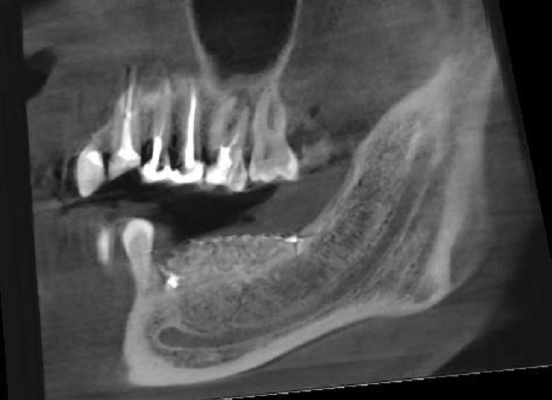

Нервы мы не видим, но видим их каналы:

Под пунктиром новая кость, выращенная для будущих имплантатов, а тёмная полоска ниже — это нижнечелюстной канал с нервом и сосудами, причина, из-за которой весь сыр-бор с аугментацией.